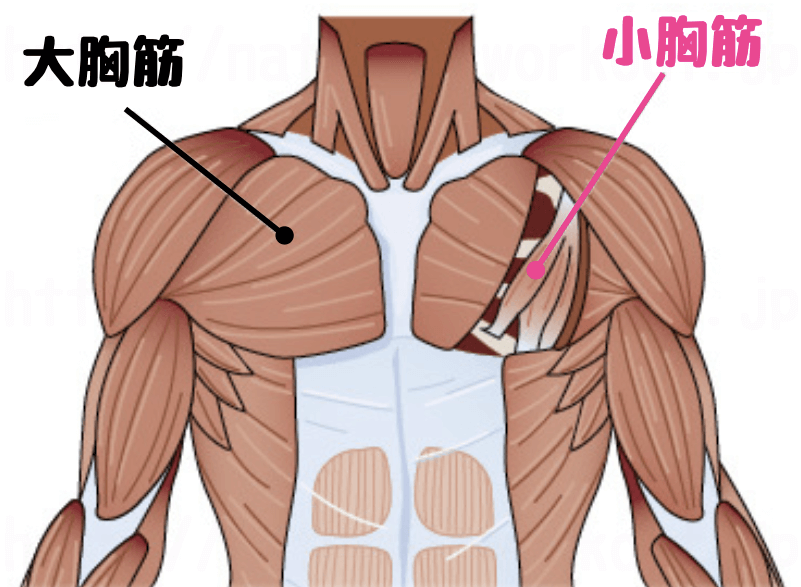

そこで、今回このテーマで注目していただきたいのでが「小胸筋(しょうきょうきん)」です。

字を書いての如く「ちいさい胸の筋肉」です。

そのまんまじゃないかい!!と突っ込みが入りそうですが(笑)、胸の奥にある筋肉です。

実はこの小胸筋という筋肉は体の前側にあるのですが、肩甲骨の上の方「烏口突起(うこうとっき)」という場所についていて、筋肉が縮こまると肩甲骨を前側に傾かせてしまいます。